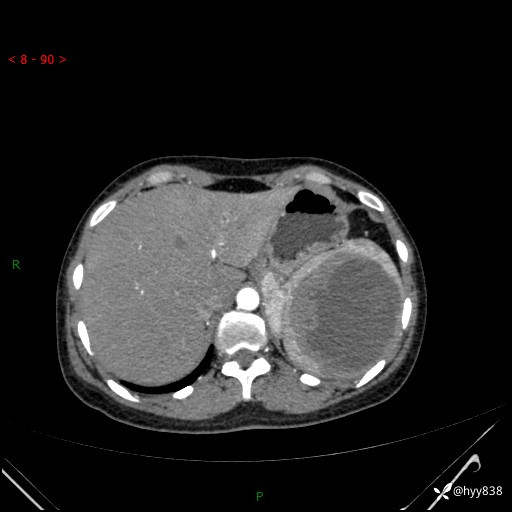

患者性别:男

患者年龄:44岁

主诉:外院超声发现脾脏占位,来我院进一步诊治。

辅助检查:CT

临床诊断:脾脏占位

脾脏CT平扫+增强(动脉期+静脉期)